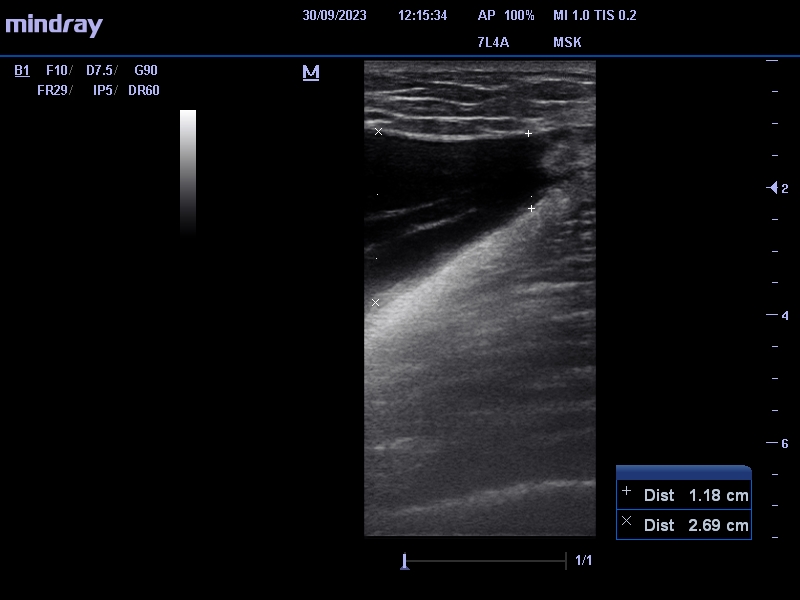

Se identifica entre el tejido celular subcutáneo y la fascia muscular, colección anecogénica, avascular de 2,8 x 17 cm (antero-posterior x craneocaudal) que nos sugiere lesión de Morel-Lavallée.